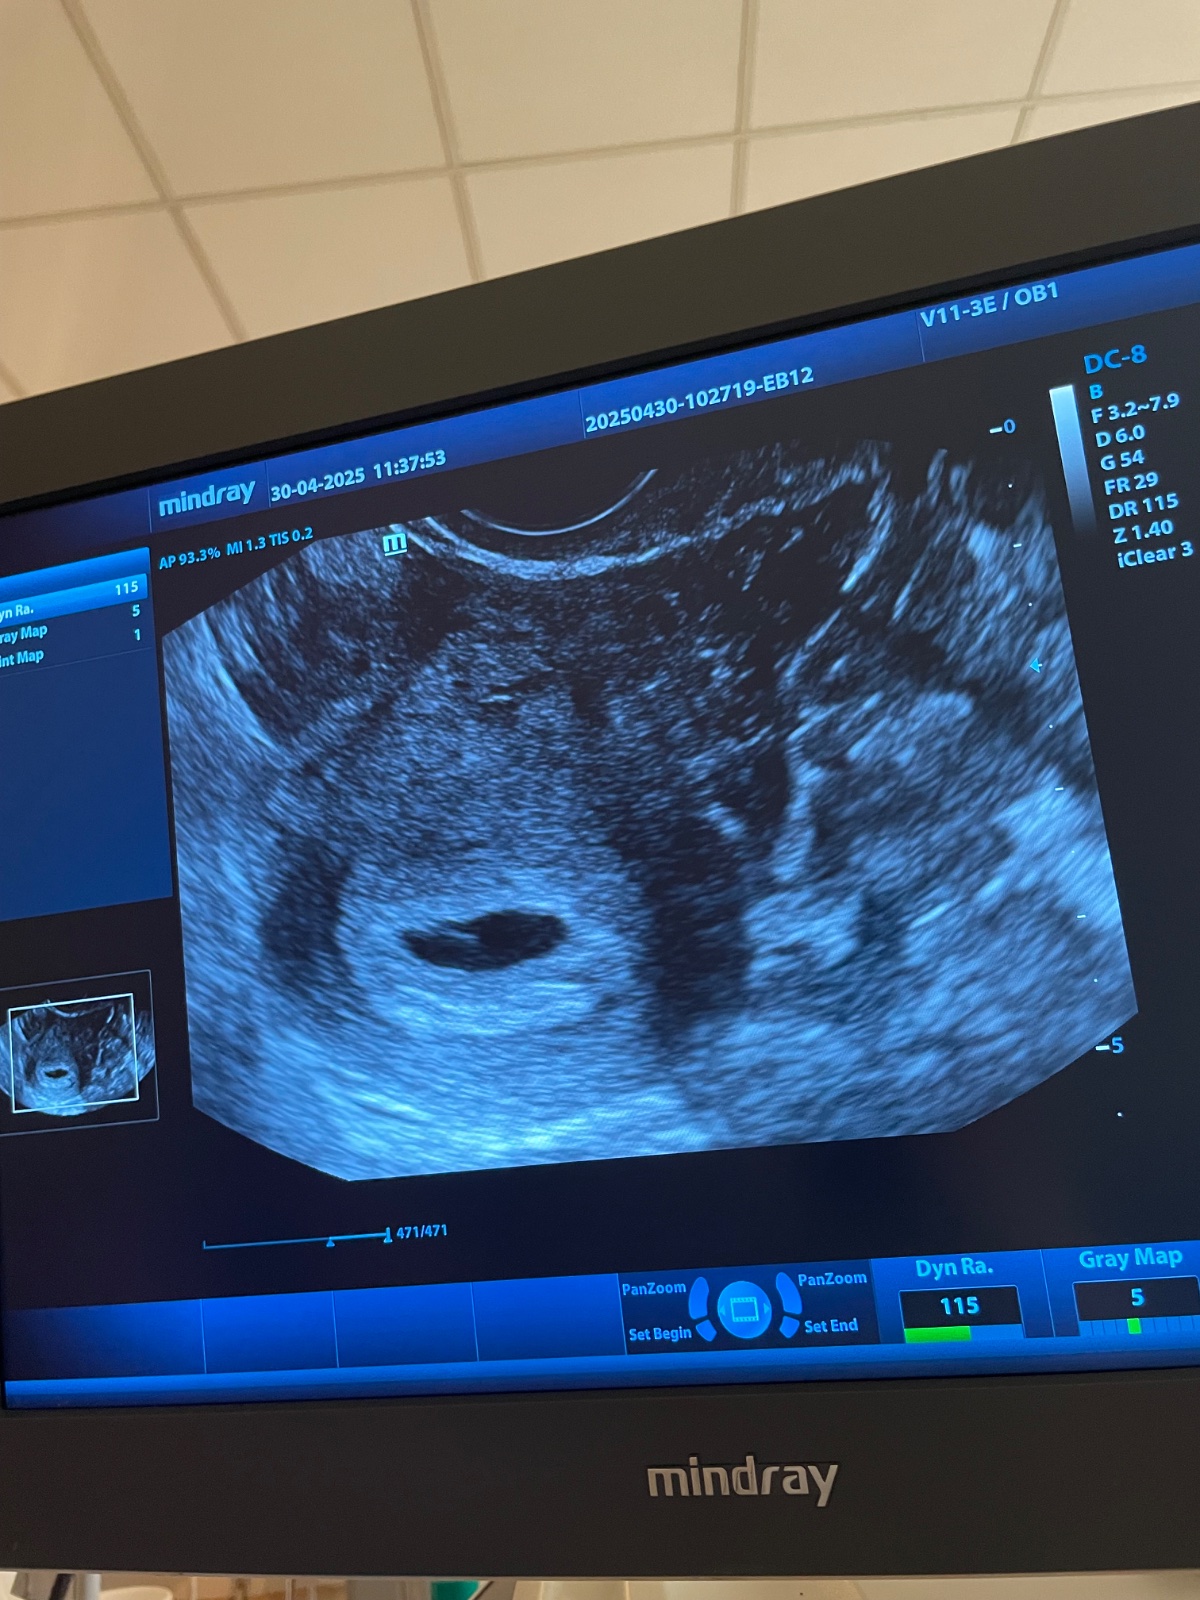

Viditeľnosť bábätka na ultrazvuku v 5. až 6. týždni

Ahojte, mala som pozitivne testy. Zajtra idem k lekarke. Podla poslednej MS by som mala byt v 5.-6.tyzdni. Ja viem ze je to este skoro, no je tam nieco vydiet v takom skorom tyzdni? Kedy u babätka zacina tlkot srdiecka? Dakujem 😊

V 5-6 tt staci, ak potvrdi tehotenstvo v maternici a vyluci mimomaternicove. Mal by tam byt gestacny vak, mohol by byt vidiet aj zltkovy vak, dokonca mozno aj embryonalnu strukturu. Srdiecko moze byt ale vobec este nemusi . zalezi od ovulacie, ak bola trochu neskor uplne staci potvrdit gestacny vak v maternici.

Takze u mna nebolo vobec nic vydiet 😞😞😞. Tehotensky test z mocu bol aj u lekarky pozitivny. Zobrala mi krv, a vo stvrtok mam ist zase na krv.

Tak dnes rano som zacala slabucko krvacat. Sla som hned k lekarke. Na sone videla malu bodku. No bohuzial HCG nestupa tak akoby malo. V utorok som mala 156 a vysledky zo stvrtku su nieco nad 190. Lekarka tomu sance nedava a nech sa pripravym na potrat alebo mimomaternicove tehotenstvo 😥